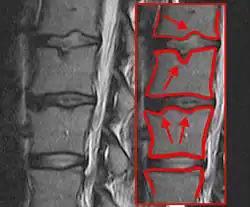

Pathogenese

Während des pubertären Wachstumsschubes zwischen dem 11. und dem 15. Lebensjahr bei Mädchen und dem 12. bis 17. Lebensjahr bei Jungen ist die Wirbelsäule besonders anfällig für Fehlentwicklungen. Bei vermehrter Biegebelastung, z. B. durch langes gebeugtes Sitzen (deswegen im Volksmund auch „Schneider-Buckel“ oder „Lehrlings-Buckel“ genannt) und bei gleichzeitig schwacher Rückenmuskulatur (fehlender Gegenzug) werden meist im Bereich der unteren Brustwirbelsäule die Wirbelkörper an den konkavseitigen ventralen Vorderkanten unverhältnismäßig stark belastet, und es kommt zu Schäden an den Knorpel-Knochen-Verbindungen der Deck- und Bodenplatten der Wirbelkörper. Dabei wird die Wachstumszone an den Wirbelkörperkanten beschädigt, wodurch die Wirbelkörper vorne langsamer und keilförmig wachsen. In den zerklüfteten Deck- und Bodenplatten entstehen kleine linsen- bis erbsengroße Kavernen, die mit Bandscheibenmaterial gefüllt sind und als Schmorl-Knorpelknötchen bezeichnet werden. In gravierenden Fällen treten Deckplatteneinbrüche auf. Meistens ist die Distanz der Wirbelkörper zueinander im Verhältnis zur normalen Wirbelsäule stark verringert. Dadurch gerät die Wirbelsäule in eine Fehlstatik. Durch die Keilform mehrerer Wirbelkörper kommt es zur Rundrücken- oder Buckelbildung, d. h. zur verstärkten Kyphosierung der Wirbelsäule. Oft entsteht kompensatorisch im Bereich der Lendenwirbelsäule ein verstärktes Hohlkreuz (Hyperlordose) mit Bildung von Tonnenwirbeln (Erhöhung der Wirbelkörper). Ebenfalls kann es zur Lyse in den Wirbelbögen mit konsekutivem Wirbelgleiten kommen.